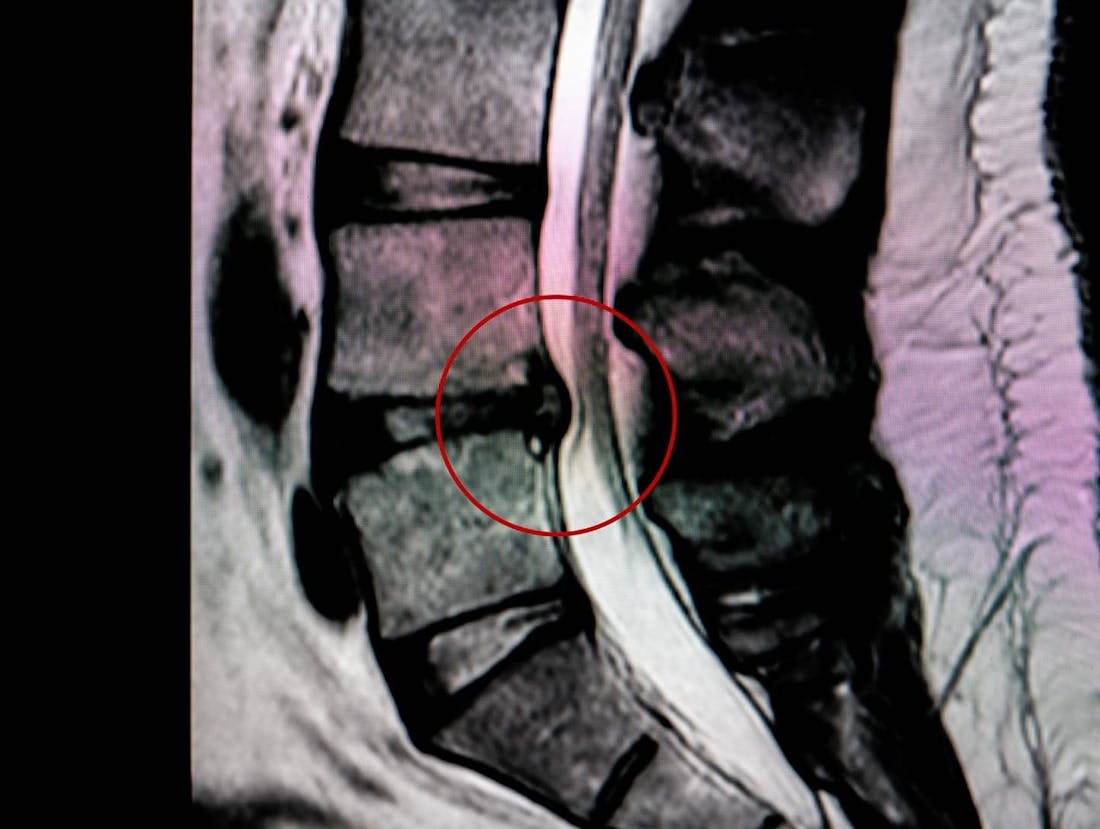

One of the most performed orthopedic procedures, discectomy removes part of a herniated disc. Removing the material frees the nerves from pressure and irritation.

Microdiscectomy

Microdiscectomy follows essentially the same operative procedure as traditional discectomy, but this newer approach requires a much smaller incision; it reduces the risk of damage to nearby parts of the spine; and patients tend to recover faster.

Lumbar Disc Microsurgery

This minimally invasive procedure relieves pressure on nerve roots caused by a herniated disc. It can eliminate the pain of sciatica.